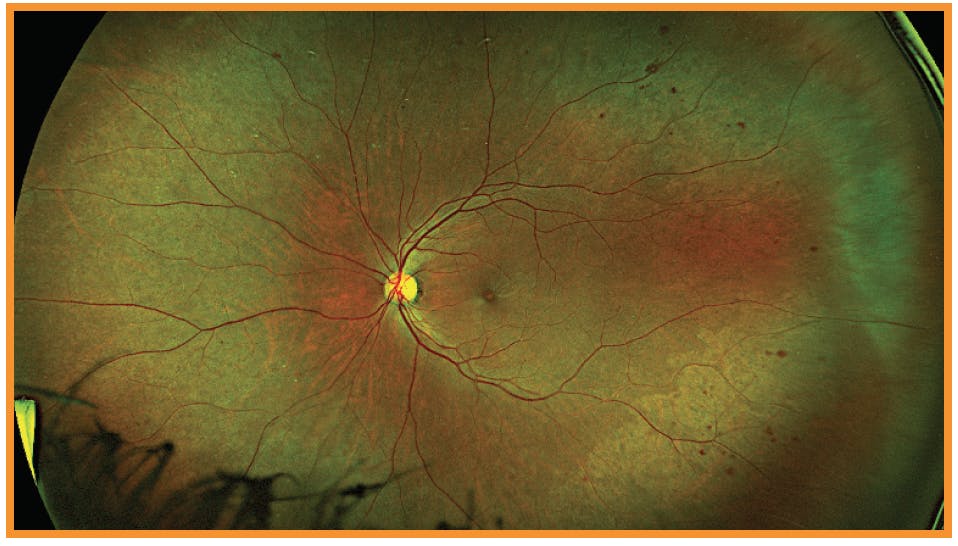

CASE 3: Uncontrolled A1C but Good Vision

Dr. Ferrucci: Our next case is a 44-year-old male who has had type 2 diabetes for about 15 years. His A1C was not as well controlled at 10, but he has relatively good vision at 20/25 each eye. His right eye (Figure 4) shows extensive hemorrhaging in all four quadrants, but the OCT looks good; there doesn’t appear to be any DME. The left eye, however, has more advanced problems (Figure 4), with additional hemorrhaging and venous beading nasally to the optic nerve. The OCT shows very close to center-involved DME.

The patient has severe NPDR in both eyes, but it’s more obvious in the left eye. I recommend referring this patient to a retinal specialist for consideration of treatment for DME and DR.

Dr. Wykoff: This case is an excellent example of a topic in DR that is being actively studied and debated in the retina community. How do you manage patients with moderately severe to severe NPDR, either without DME or with minimal DME, and very good vision? Also, how does the presence or absence of DME change how you think about his patient?